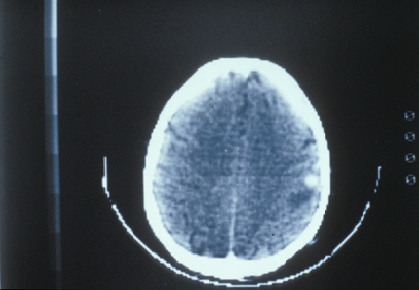

Dans de rares cas, le LNH se développe exclusivement dans le système nerveux central qui comprend le cerveau, l’œil, les méninges et la moelle épinière. On parle alors de lymphome cérébral primitif (LCP) ou de lymphome intra-oculaire primitif (LIOP).

• L’IRM (imagerie par résonance magnétique) cérébrale pour les lymphomes cérébraux. Une IRM est semblable à une tomodensitométrie, par contre, elle utilise des champs magnétiques à la place des rayons X.